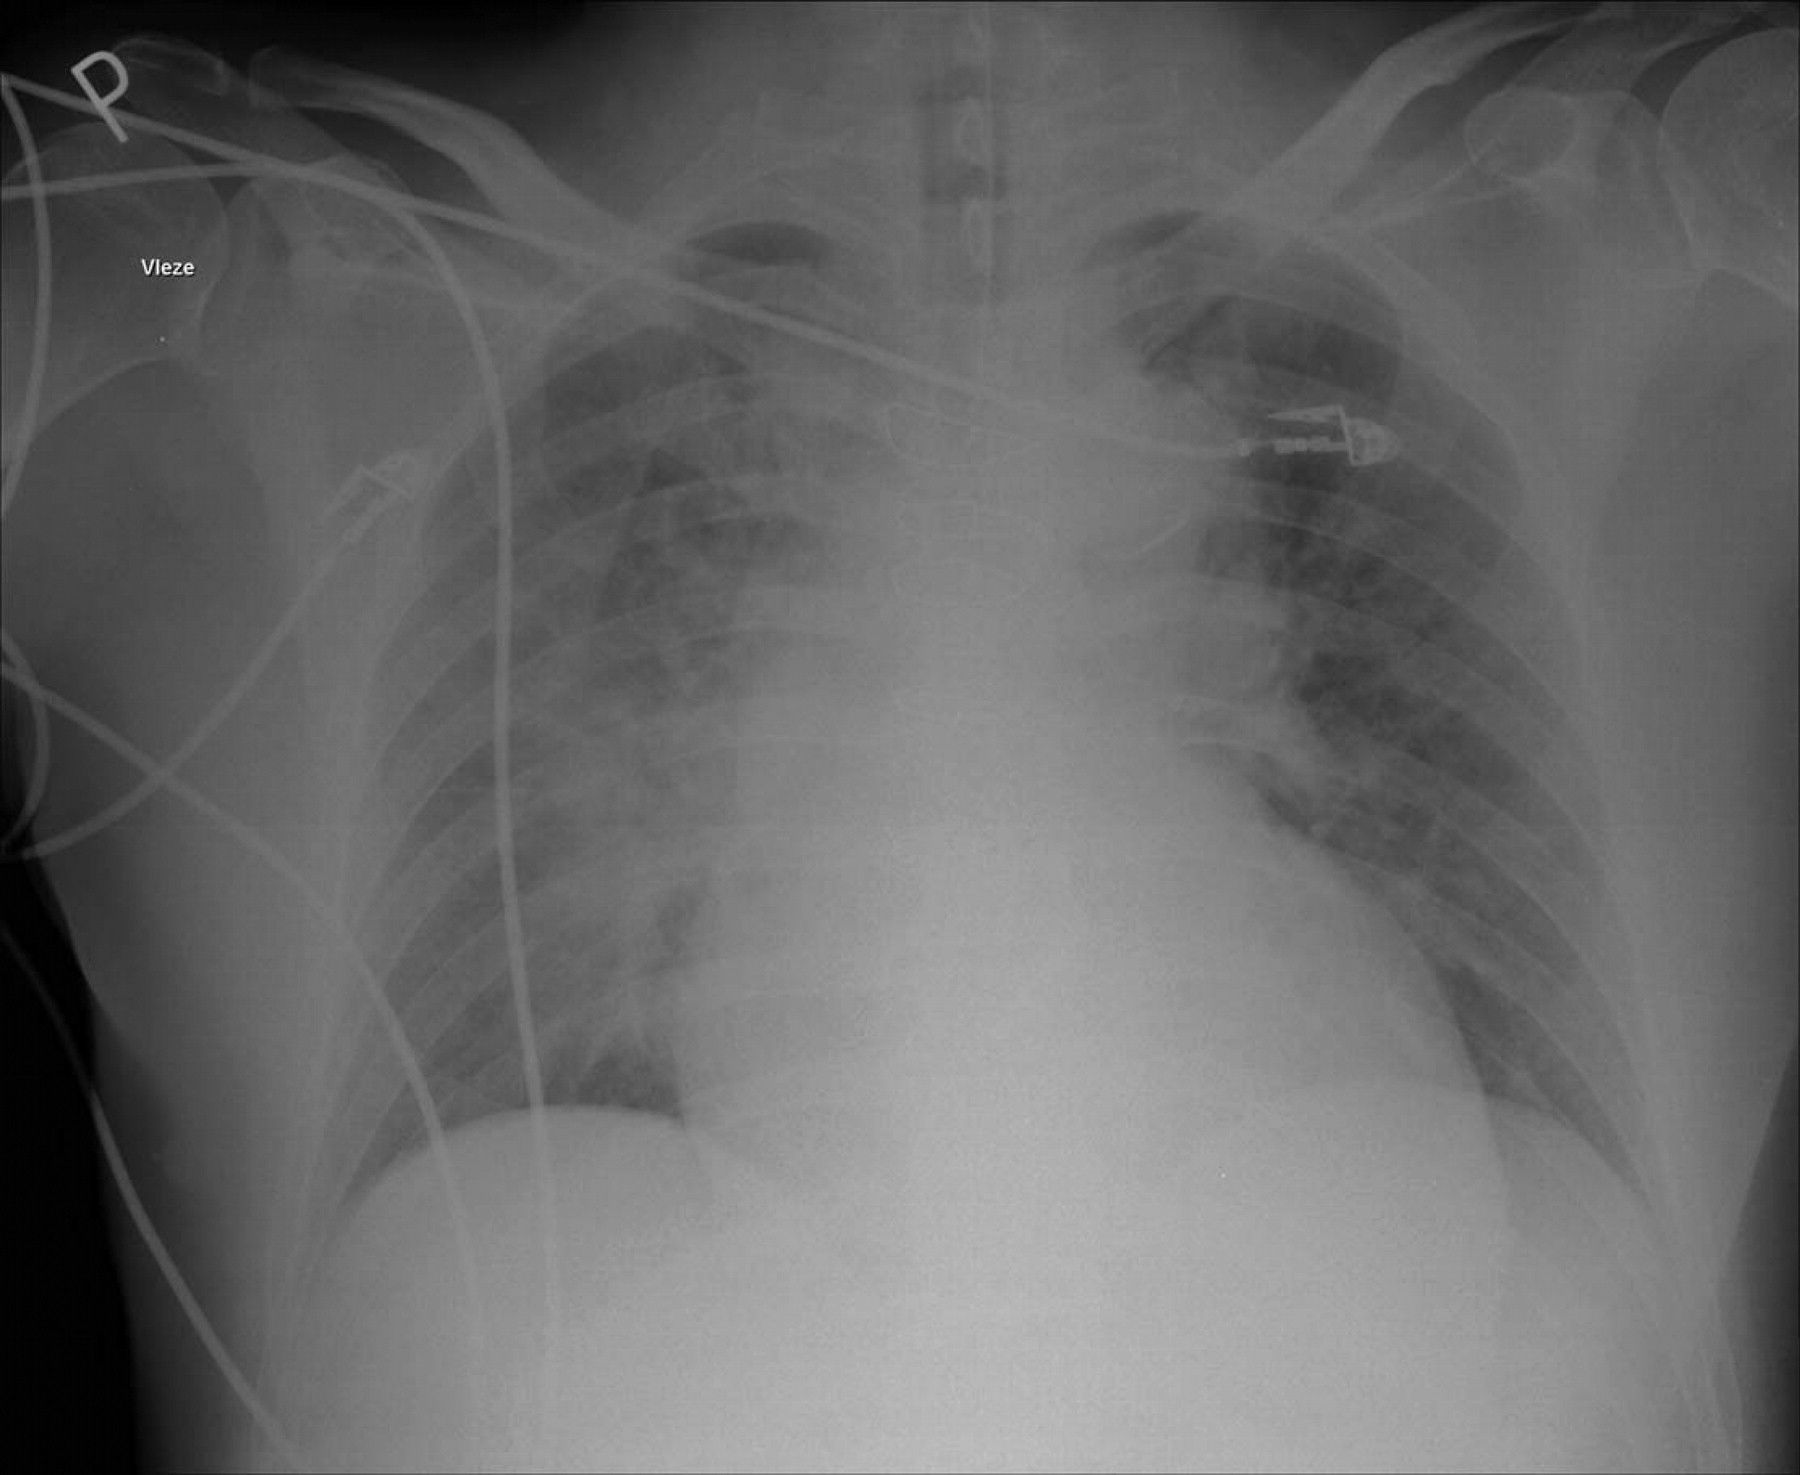

1. Chest X-Ray

1. Pulmonary edema